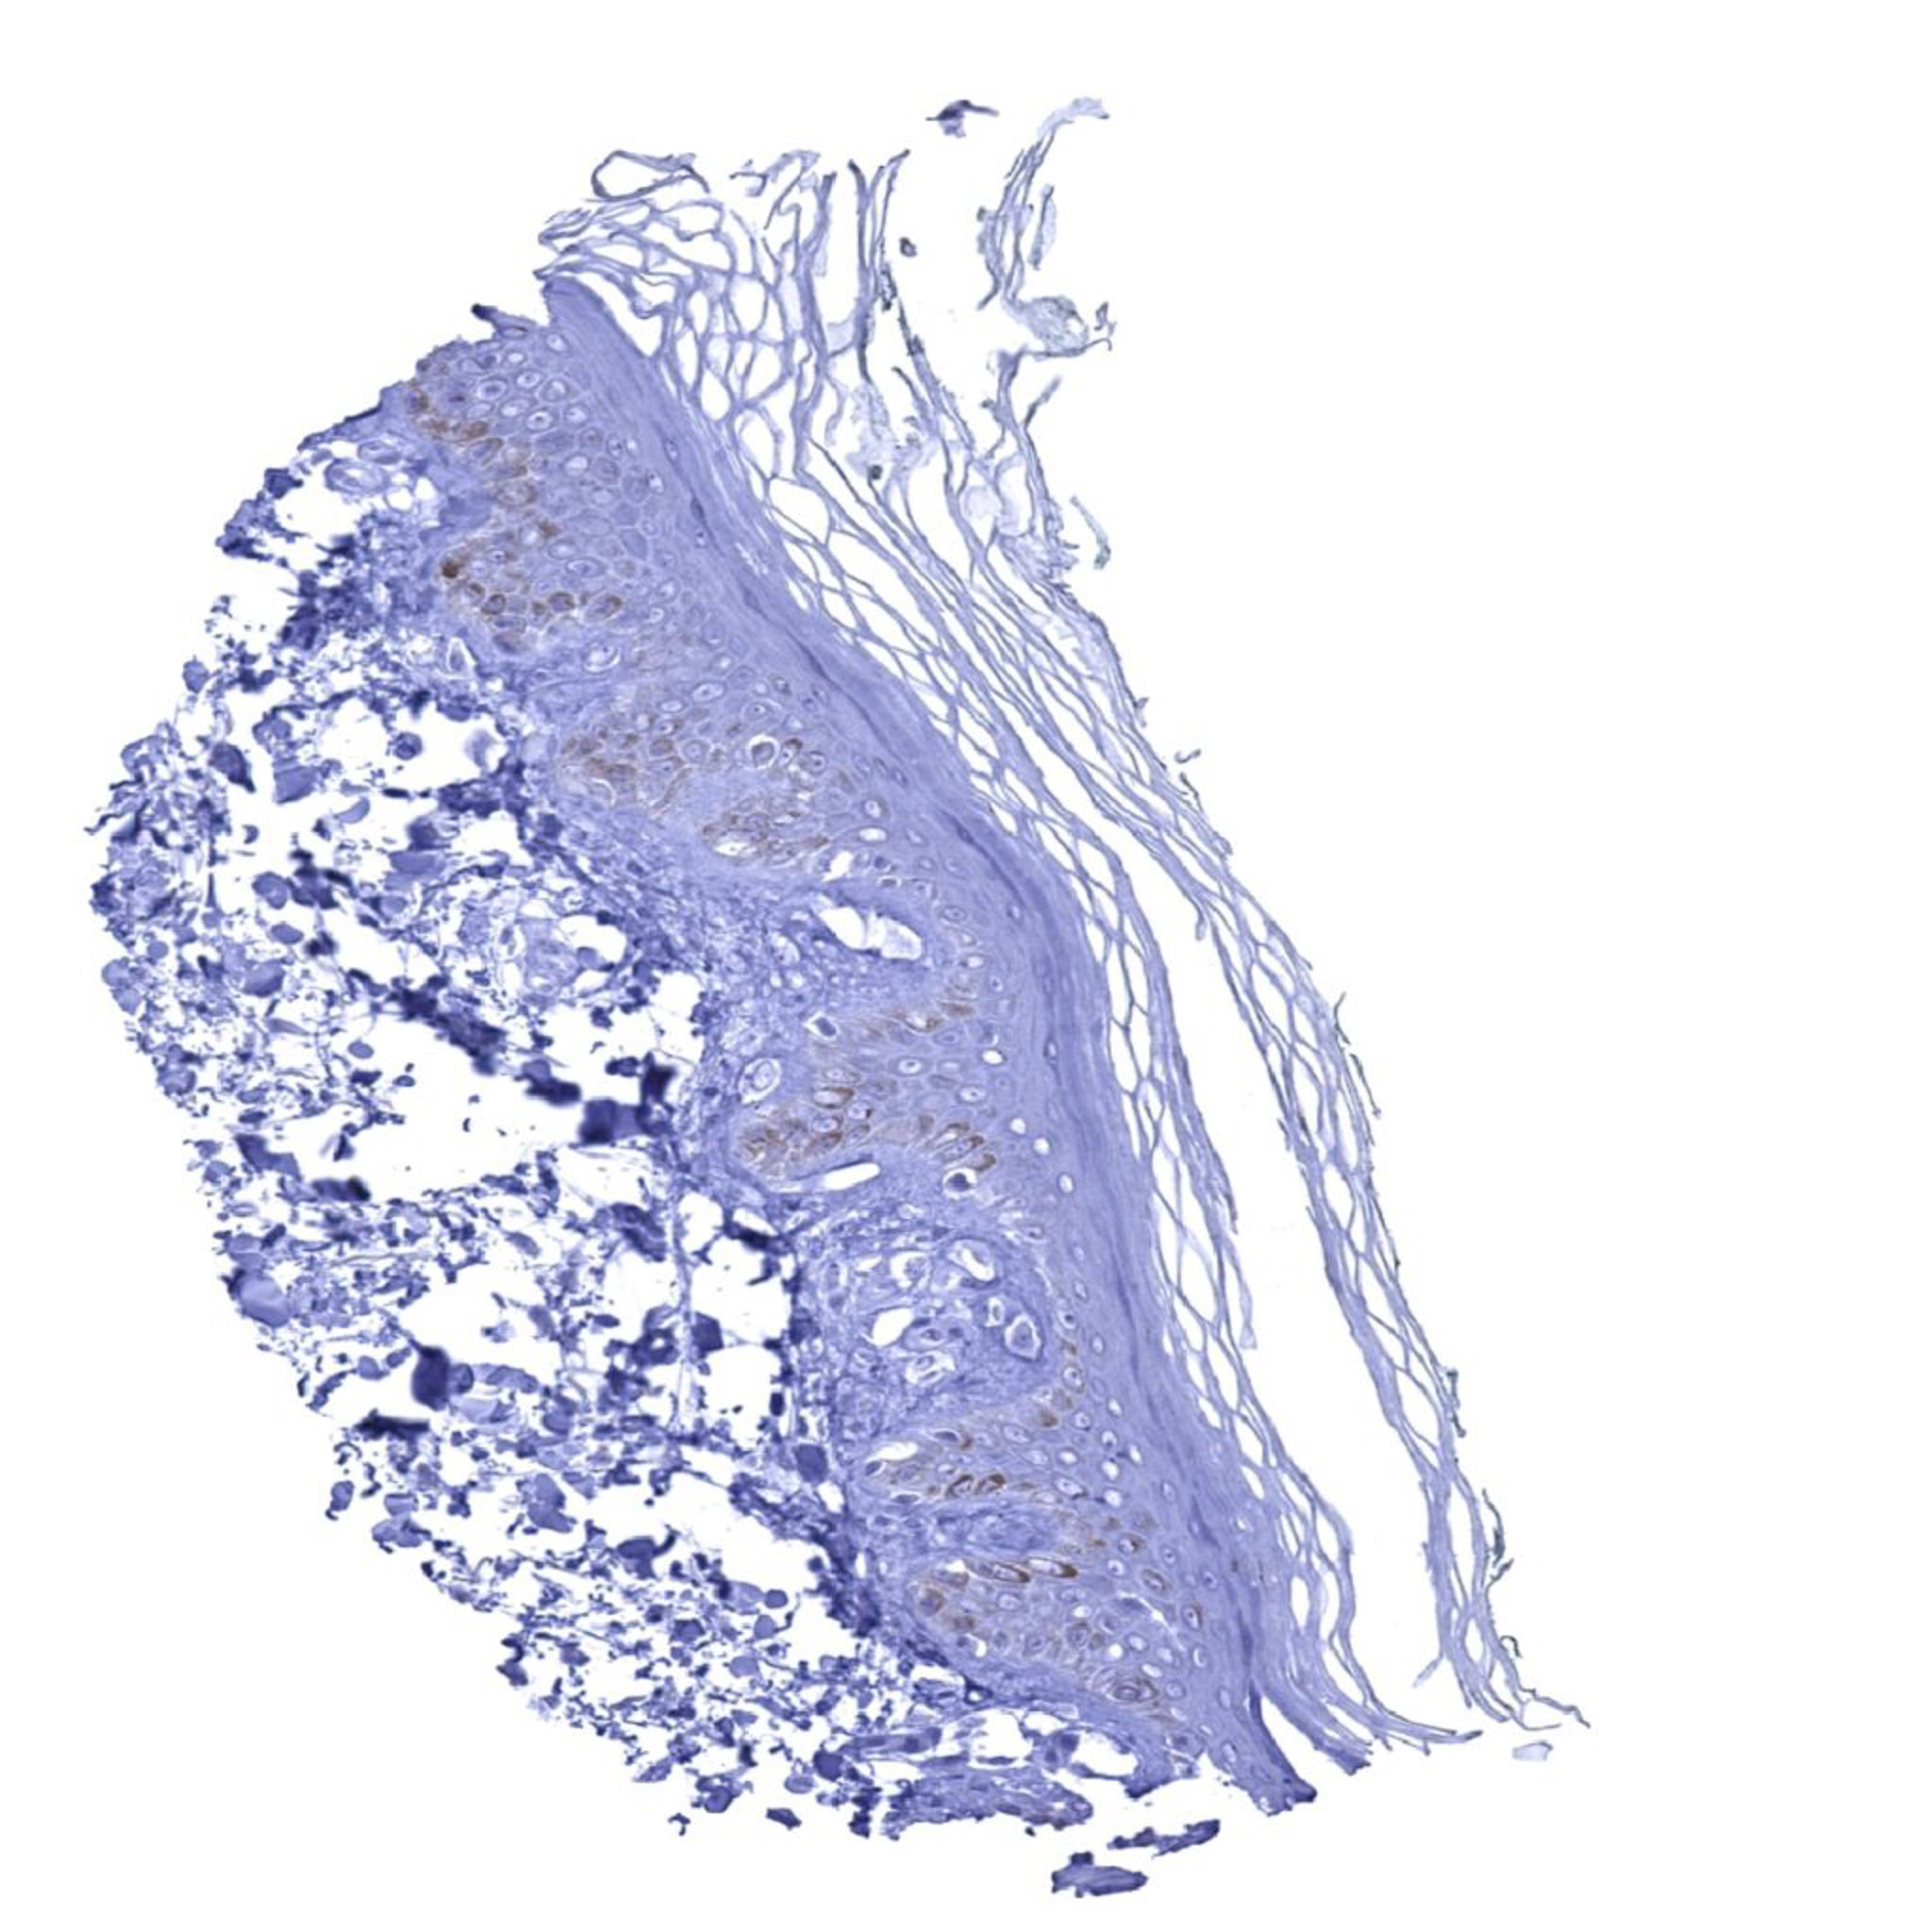

Skin – UPK1B immunostaining is absent in keratinizing squamous epithelium of the skin.